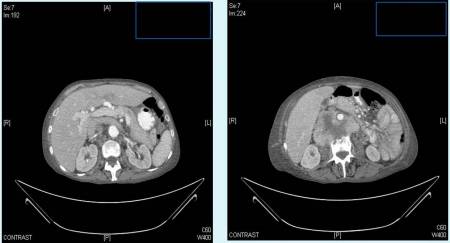

En la radiografía de tórax se apreciaba derrame pleural derecho y en el TAC de abdomen una masa retroperitoneal heterogénea que englobaba, comprimía y desplazaba ventralmente la vena cava inferior y la aorta […], con afectación del cuerpo vertebral de L3.

Todos estos hallazgos fueron sugerentes en primera instancia de sarcoma peritoneal, confirmados posteriormente tras su ingreso en planta.